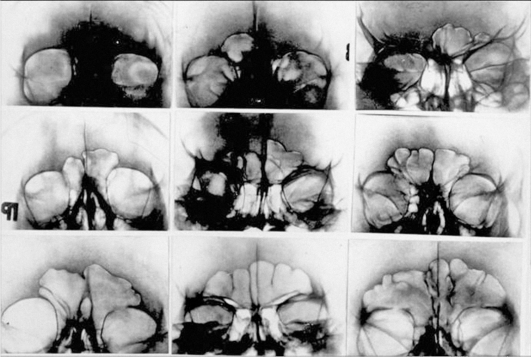

При внутреннем исследовании неопознанных трупов обращают внимание на возрастные изменения внутренних органов, и в частности сердечно-сосудистой системы, на аномалии внутренних органов, которые могли быть установлены при жизни (например, наличие одной подковообразной почки), заболевания и следы перенесенных операций (аппендэктомия, холецистотомия и др.) и костных травм.

При наличии следов врачебных вмешательств на зубах, качество которых указывает на социальный статус погибшего, следов заживших травм и особенностей скелета следует сделать рентгенографию челюстей, придаточных пазух черепа и костных повреждений тела. В дальнейшем эти снимки можно будет сравнить с рентгеноснимками пропавшего без вести человека с целью идентификации его личности. Если череп по тем или иным причинам изъять не удается, желательно изготовить гипсовые модели зубов и челюстей (с помощью зубного техника или протезиста), которые целесообразно использовать при отождествлении личности по зубным протезам погибшего, в том числе по съемным.

При экспертизе гнилостного трупа секционное исследование необходимо не только с целью установления причины наступления смерти, но и выявления болезненных и возрастных изменений различных органов, что, несомненно, имеет идентификационное значение. Диагностические возможности судебномедицинской экспертизы в этом случае зависят прежде всего от степени развития гниения и распада органов и тканей.

Патологически измененные внутренние органы, как правило, сохраняют лучше свое гистологическое строение, чем неизмененные. Так, при далеко зашедшем процессе гниения можно определить болезненные изменения клапанного аппарата сердца, сосудов и имеющийся атеросклероз.

Поля рубцовой ткани обнаруживаются даже при значительном развитии аутолитических процессов в мышце сердца.

Болезненные изменения в легких в виде абсцессов, каверн и петрификатов удается обнаружить в тех случаях, когда легочная ткань еще не подверглась высыханию или гнилостному расплавлению.

Головной мозг сохраняет свой обычный вид в течение 7-8 мес, а иногда и несколько десятков лет (как это было выяснено при эксгумации останков царской семьи в 1991 г.). При его исследовании удается выявить патологические изменения и признаки ЧМТ.

Язвы желудка с большим соединительным валом, раковые и доброкачественные опухоли (полипы и др.) желудка сохраняются до аутолиза его стенки.

Воспалительные заболевания печени (цирроз, абсцесс, жировая дистрофия) хорошо выявляются при гистологическом исследовании, так же как и хронические изменения почек с образованием рубцов.